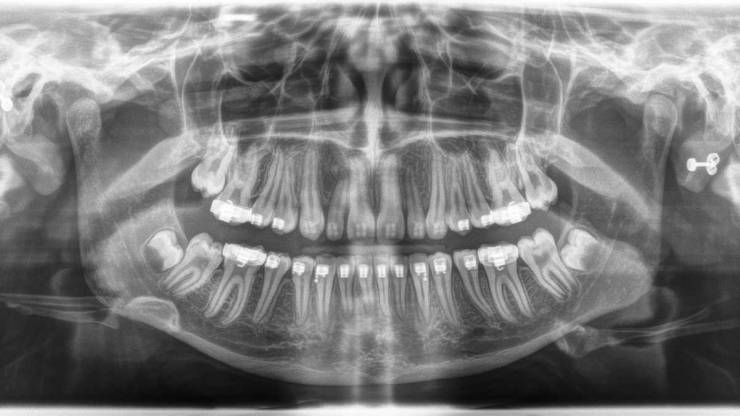

Digitalna ortopan snimka

Ortopantomogram (skraćeno ortopan) snimanje predstavlja 2D rentgensku snimku svih zubi gornje i donje vilice s okolnim anatomskim strukturama. Intraoralna dentalna slika daje prikaz pojedinačnog zuba, detalje krune i korijena te okolnih struktura parodonta i alveolarne kosti.

Digitalni ortopan označava korištenje najsuvremenije digitalne tehnologije prilikom snimanja.